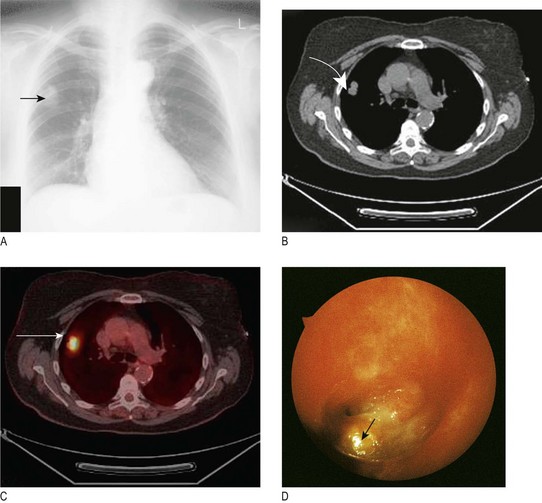

In superior vena caval obstruction (SVCO) (Fig. 7.11A) the JVP is raised and non-pulsatile, and the abdominojugular reflex is absent. Most cases are due to lung cancer compressing the superior vena cava. Other causes include lymphoma, thymoma and mediastinal fibrosis. Facial flushing, distension of neck veins and stridor can occur in SVCO when the arms are raised above the head.

Skin: Subcutaneous lesions may be visible, including metastatic tumour nodules, neurofibromas and lipomas, as may vascular anomalies, e.g. the dilated venous vascular channels of SVCO (Fig. 7.11B).